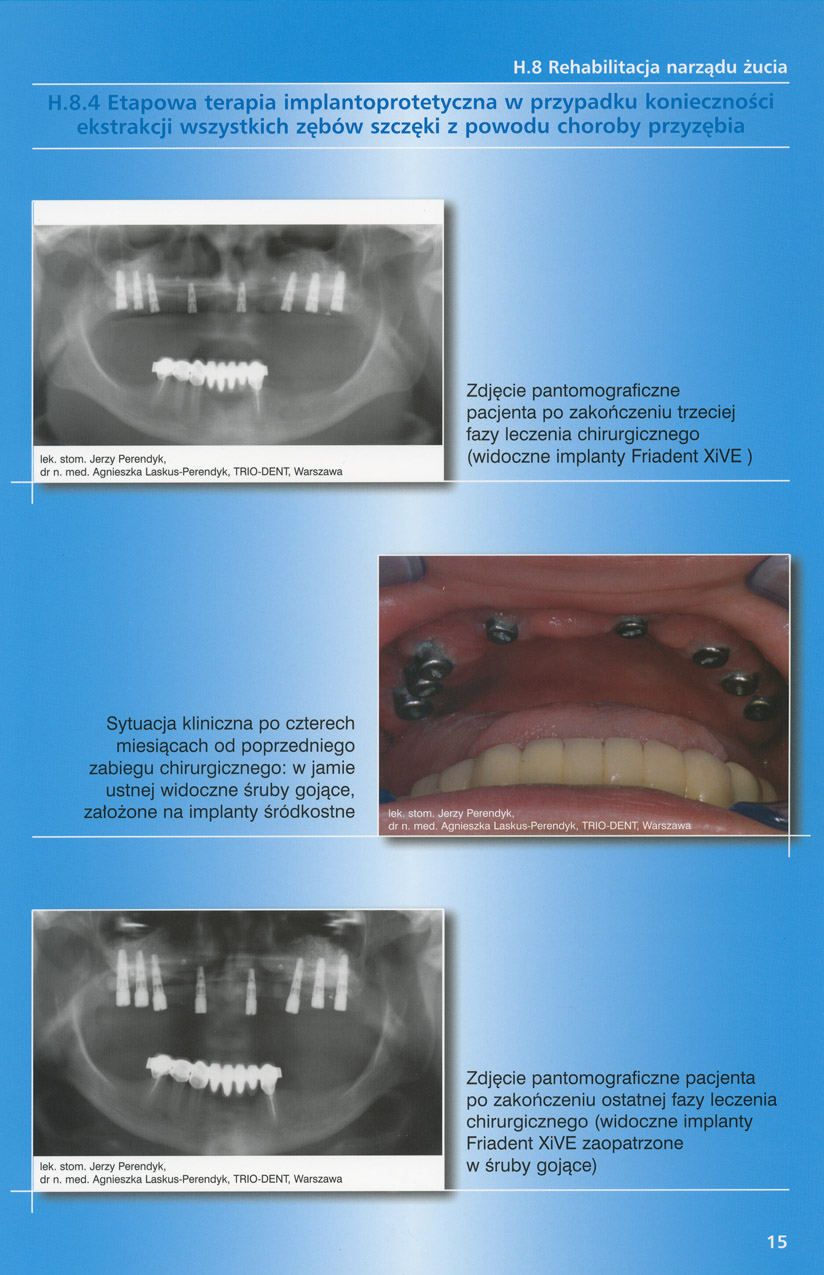

zobacz więcejGaleria przypadków klinicznych, obrazująca proces terapeutyczny od stanu wyjściowego aż do oddania ostatecznej pracy uzupełnienia brakującego uzębienia.